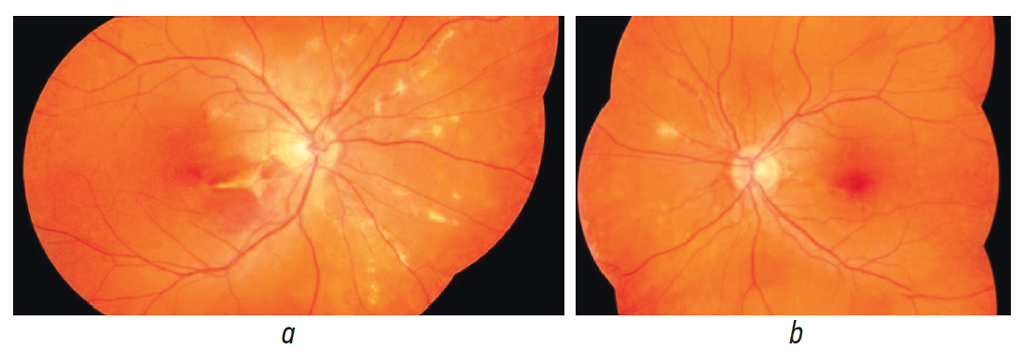

Пациентке выполнена аутофлуоресценция глазного дна (рис. 5) и флуоресцентная ангиография (ФАГ) (рис. 6). На обоих глазах выявлена гипоаутофлуоресценция ангиоидных полос в перипапиллярной зоне, а также просачивание и накапливание в поздней фазе красителя в парафовеальной зоне.

Рис. 5. Изображение глазного дна правого (a) и левого (b) глаза в режиме коротковолновой аутофлуоресценции, очаги гипоаутофлуоресценции в перипапиллярной и папилломакулярной зонах

Fig. 5. The fundus image of the right eye (a) and the left eye (b) in the short-wave autofluorescence mode, there are hypoautofluorescence loci in the peripapillary and papillomacular areas

Пациентка находилась под ежемесячным наблюдением в течении 3,5 лет. Острота зрения правого глаза составляет 0,8, сохраняются жалобы в виде метаморфопсий, которые не меняются, не увеличиваются с течением времени. За годы лечения увеличилась зона атрофии по ходу ангиоидных полос, сформировался рубец с зоной географической атрофии вокруг. Длительное время признаков активности процесса нет (рис. 7, а).

Рис. 7. Фотография глазного дна правого (a) и левого (b) глаза на последнем визите

Fig. 7. The fundus photo of the right eye (a) and the left eye (b) at the last visit

В левом глазу также сохраняется высокая острота зрения (1,0), пациентку не беспокоит ухудшение зрения, отсутствуют жалобы на метаморфопсии. Активность парафовеолярной мембраны наблюдалась в виде периодически возникающих субретинальных кровоизлияний <1/4 ДД, которые субъективно не беспокоили пациентку (рис. 7, b). На момент последнего осмотра отсутствие активности хориоидальной неоваскуляризации по данным ОКТ и ФАГ сохраняется.